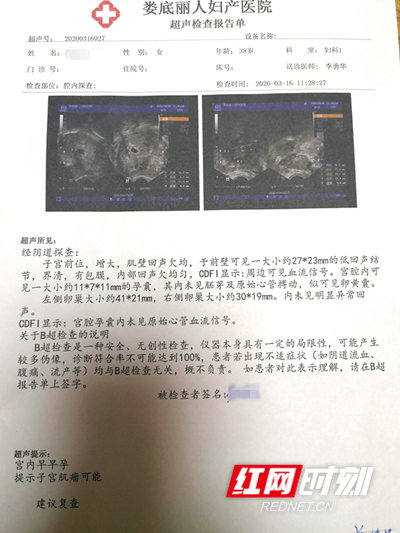

宫外孕B超

阴超词条图册_百度百科

娄底女子3次宫外孕切除一侧输卵管,这次终于怀稳了!

图片尺寸400x533